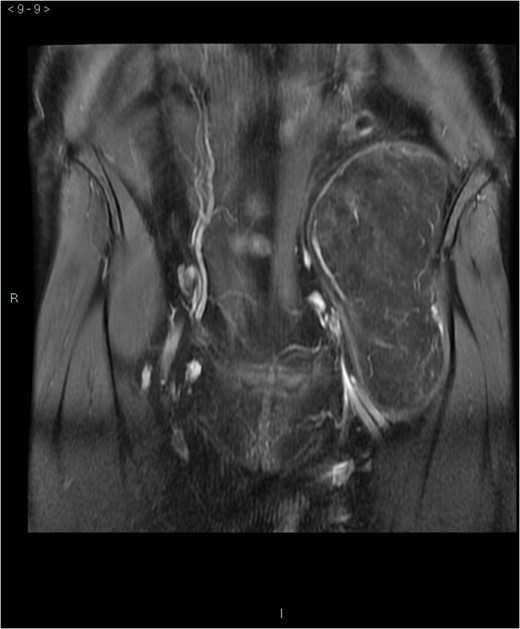

A 58-year-old woman was evaluated for lower abdominal pain, without additional symptoms. An abdominal ultrasonography revealed the presence of a 15 cm homogenous mass, located in the left pelvic cavity. Subsequent MRI showed a capsulated mass, isointense with the adipose tissue, longitudinally extending from the left inguinal area to the left leg root and located on the medial aspect of the left iliac bone. MRI also revealed within the mass some fibrotic branches containing small blood vessels. No evidence of extracapsular invasion of the surrounding structures was evident (Figs 1–6).

Preoperative differential diagnosis is mainly based on radiologic imaging and is very difficult, because no pathognomonic signs exists for diagnosis of hibernoma; usually CT-scan shows an homogenous lesion, whose density is between subcutaneous fat and skeletal muscle; MRI shows slightly lower signal intensity on T1 weighted spin-echo (T1WSE), marked enhancement and partial fat suppression on short Tau inversion recovery (STIR) and fat-saturated sequences [5].